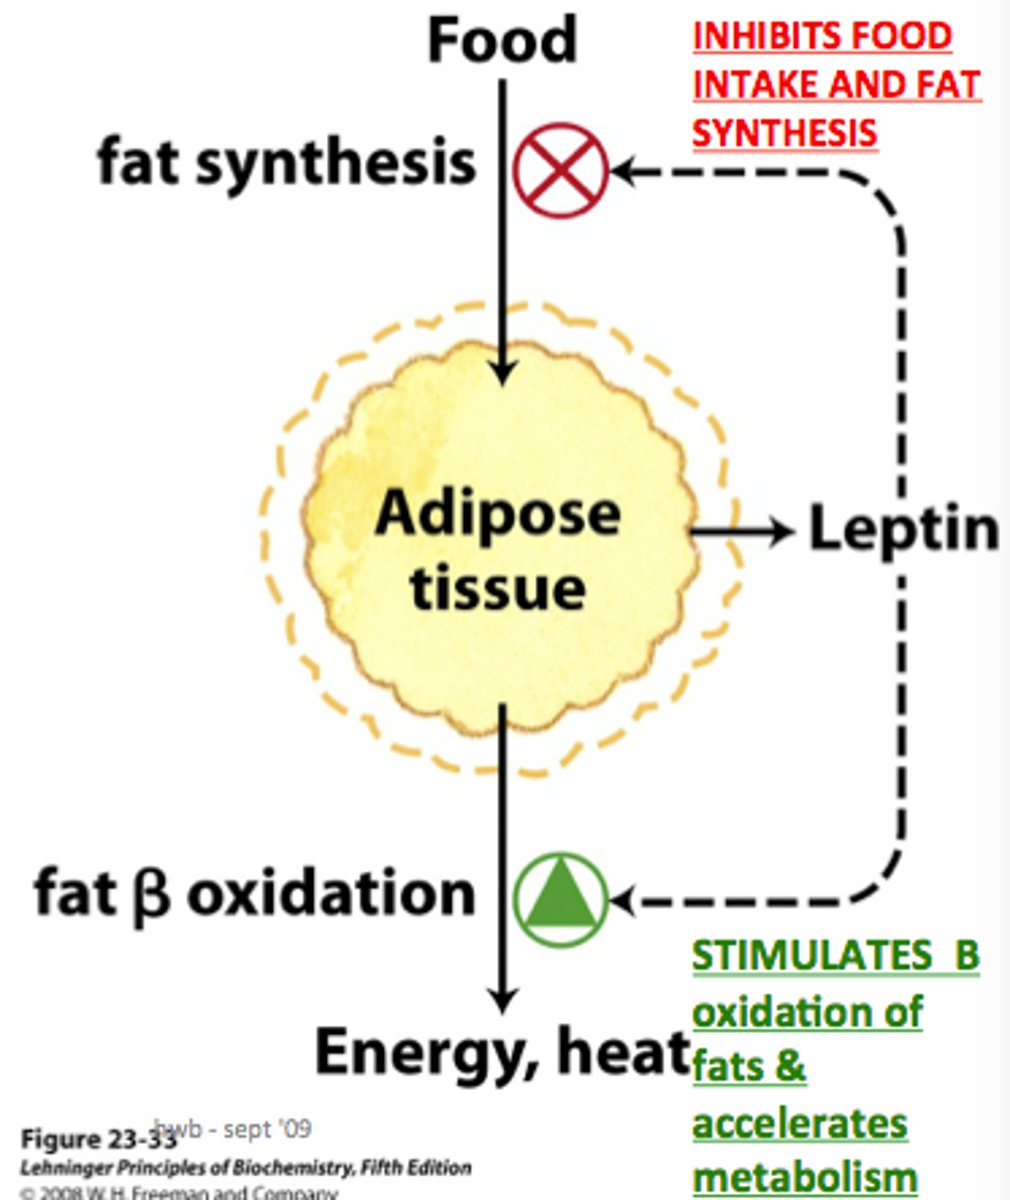

Leptin

hormone that signals the hypothalamus and brain stem to reduce appetite and increase the amount of energy used

Ghrelin

a hunger-arousing hormone secreted by an empty stomach